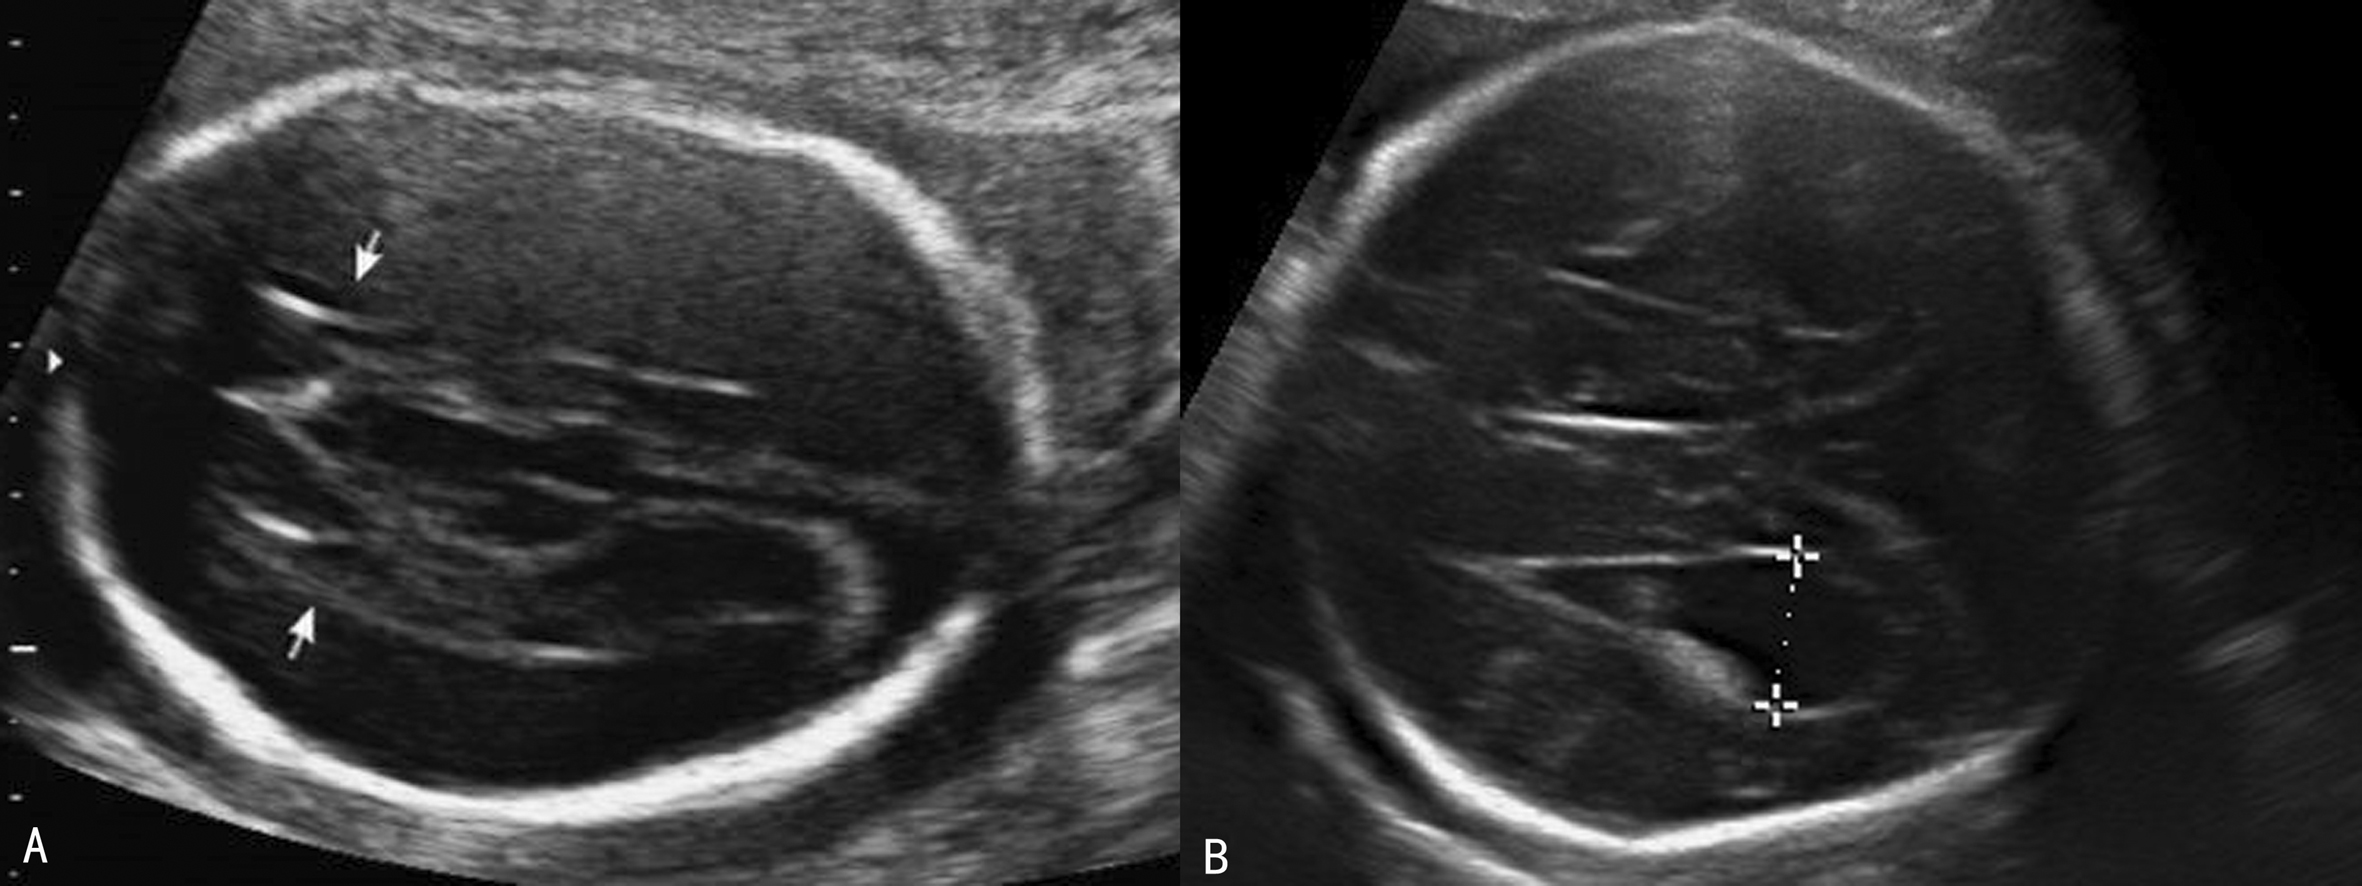

1. 侧脑室前角及侧脑室体部偏离中线,向外侧展开,侧脑室前角变窄呈尖角峰状,形成“公牛角征”(图3A)。双侧脑室呈平行状,侧脑室后角扩张,与变窄的前角一起呈现“泪滴状”(图3B)。

图3胼胝体缺失脑室变化

2. 透明隔腔消失(图4)。

图4胼胝体缺失透明隔强消失